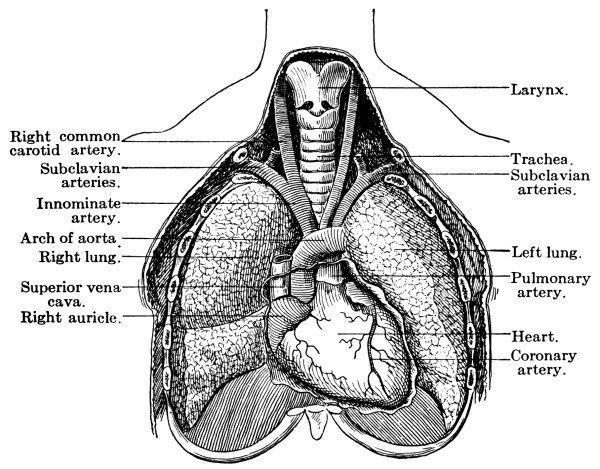

| The Heart and Circulation | 101 |

The Heart, 101—The Pericardium, 101—Cavities of the Heart, 103—The Endocardium, 103—The Valves of the Heart, 103—Circulation, 105—Circulation in the Fetus, 106—Arteries, 107—Veins, 109—Portal Circulation, 109—Pulmonary Circulation, 110—Nerves of the Heart, 110—Heart Sounds, 111—The Heart Beat, 111—Factors Affecting Circulation, 112—The Pulse, 113—Blood Pressure, 114—Nerve Supply of the Blood-vessels, 115—The Blood, 116—Composition of the Blood, 116—Coagulability of the Blood, 117—Blood-corpuscles, 118. |

The Larynx, 121—The Trachea, 123—The Thyroid Gland, 124—The Thymus Gland, 124—The Bronchi, 125—The Lungs, 125—The Pleura, 125—The Mediastinum, 126—Respiration, 127—Air, 129—Respiratory Sounds, 129—Changes in Air in Lungs, 129—Effect of Respiration on Blood, 130—Nervous Mechanism of Respiration, 130—Variations in Respiration, 131. |